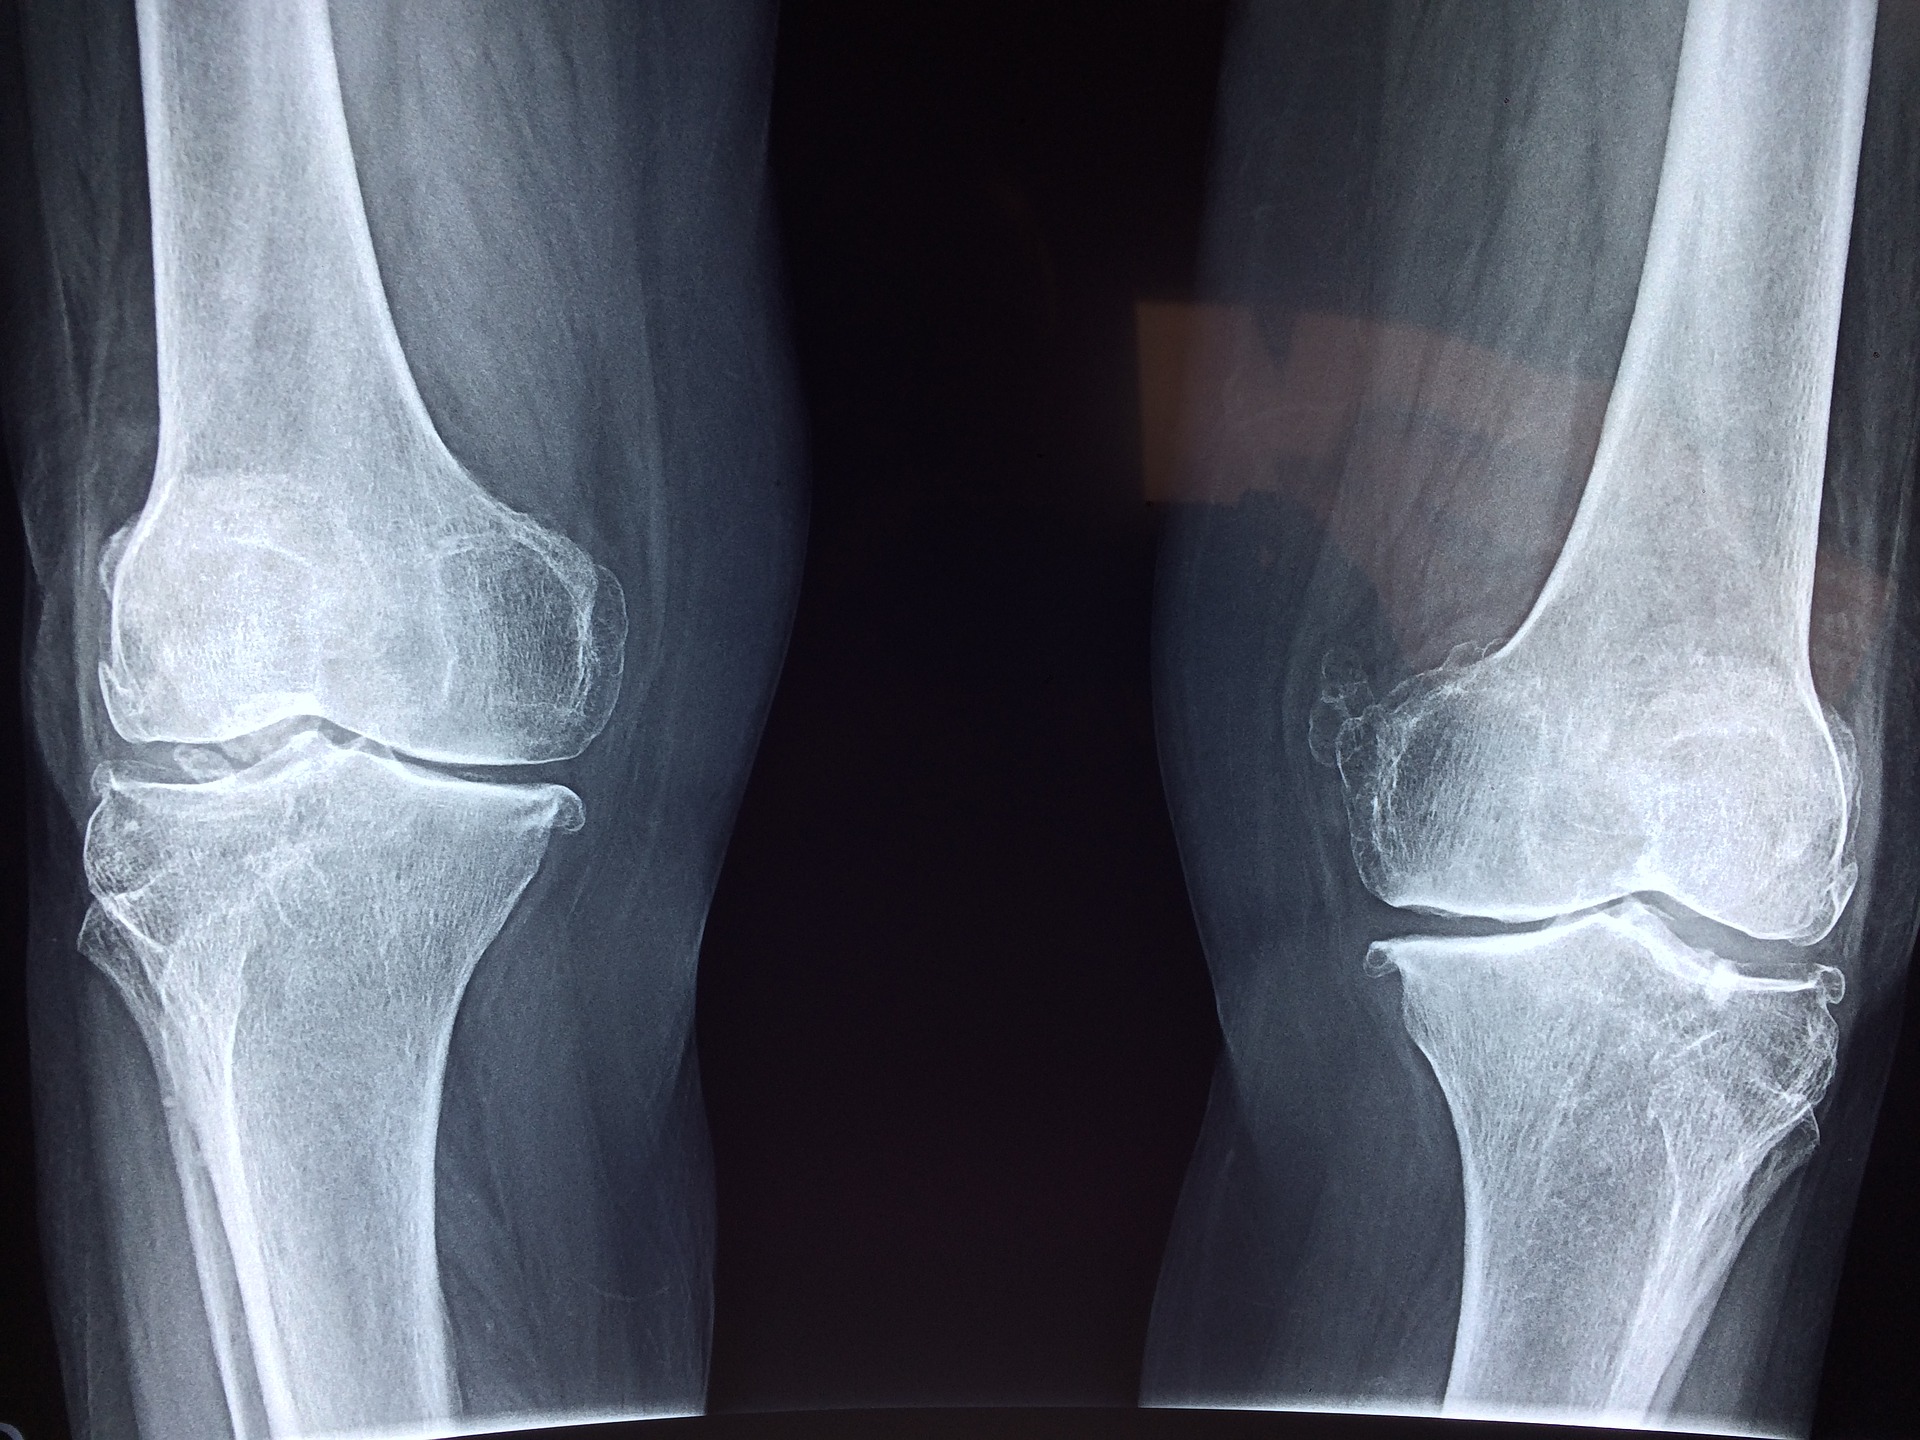

The skeleton is a highly dynamic structure that changes shape and composition throughout a person’s life. Osteocytes are the most abundant cell type in bone but have proved difficult to study because they are embedded within the hard mineral structure of the skeleton.

Inside the bone, osteocytes form a network similar in scale and complexity to the neurons in the brain (with over 23 trillion connections between 42 billion osteocytes) that monitors bone health and responds to ageing and damage by signalling other cells to build more bone or break down old bone. Diseases such as osteoporosis and rare genetic skeletal disorders arise from an imbalance in these processes.